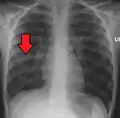

A chest X-ray showing a very prominent wedge-shaped area of airspace consolidation in the right lung characteristic of acute bacterial lobar pneumonia

A chest radiograph is frequently used in diagnosis.[23] In people with mild disease, imaging is needed only in those with potential complications, those not having improved with treatment, or those in which the cause is uncertain.[23][67] If a person is sufficiently sick to require hospitalization, a chest radiograph is recommended.[67] Findings do not always match the severity of disease and do not reliably separate between bacterial and viral infection.[23]

X-ray presentations of pneumonia may be classified as lobar pneumonia, bronchopneumonia, lobular pneumonia, and interstitial pneumonia.[73] Bacterial, community-acquired pneumonia classically show lung consolidation of one lung segmental lobe, which is known as lobar pneumonia.[41] However, findings may vary, and other patterns are common in other types of pneumonia.[41] Aspiration pneumonia may present with bilateral opacities primarily in the bases of the lungs and on the right side.[41] Radiographs of viral pneumonia may appear normal, appear hyper-inflated, have bilateral patchy areas, or present similar to bacterial pneumonia with lobar consolidation.[41] Radiologic findings may not be present in the early stages of the disease, especially in the presence of dehydration, or may be difficult to interpret in the obese or those with a history of lung disease.[24] Complications such as pleural effusion may also be found on chest radiographs. Laterolateral chest radiographs can increase the diagnostic accuracy of lung consolidation and pleural effusion.[40]